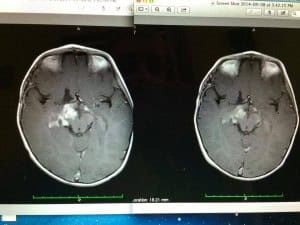

- October 16, 2014"Our 15 year old son suffers from a traumatic brain injury from just over 3 years ago. He has episodes…